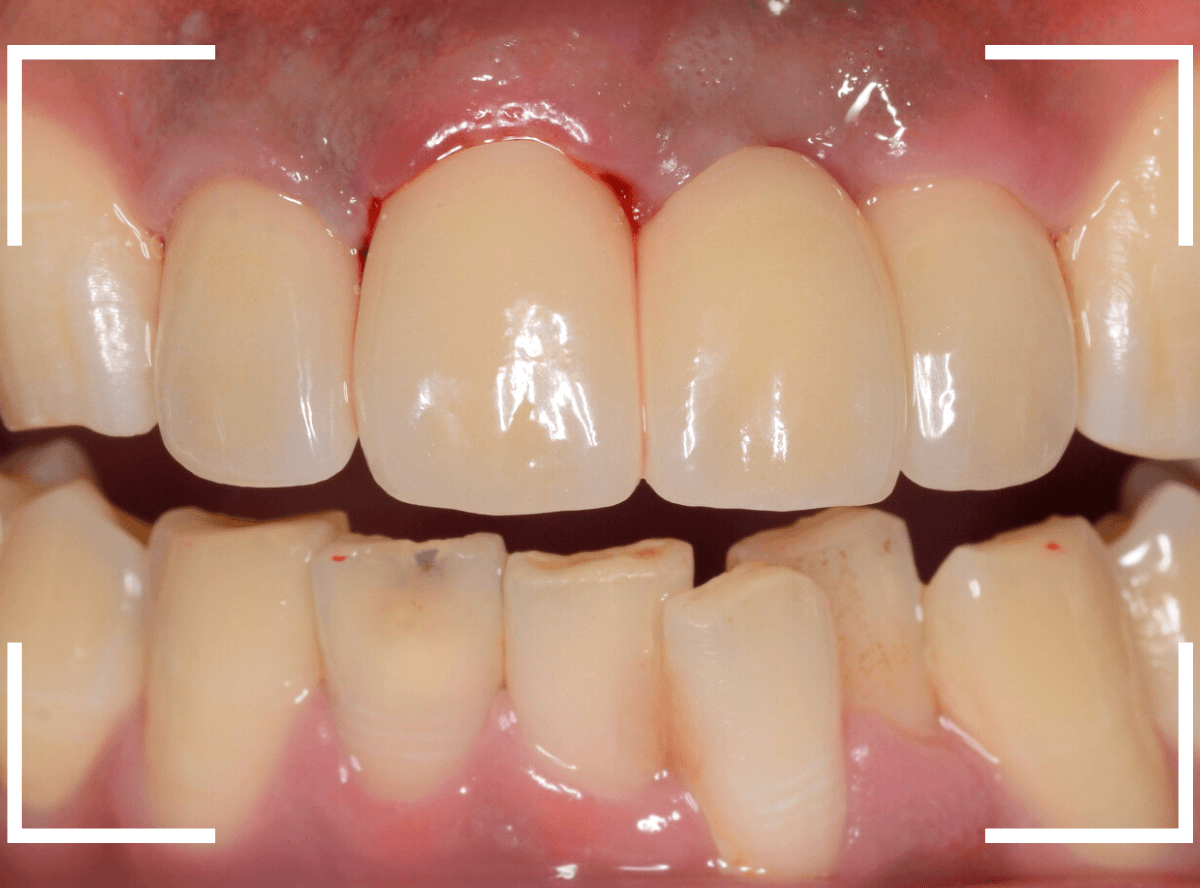

しばらく経過観察して、歯肉が落ち着いたところです。

さし歯を入れるのに心配ない程度の歯の高さが確保でき、さし歯を作るための準備が整いました。

今回は、審美性と、清掃性が高く、歯周病が進行しにくいという利点を考慮して、ジルコニア・セラミックでの治療を選択されました。

ジルコニア・セラミックset後の状態です。

仮歯で細かく調整したおかげで、下の歯のかみ合わせは若干の調整で済む事ができました。

set前との比較です。